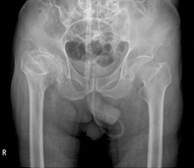

2. 인공관절시술 시행 병원(고관절 / 슬관절 / 견관절)좋은삼선병원 인공관절센터는 고관절, 슬관절, 견관절 등 다양한 인공관절시술을 시행하고 있습니다.

고관절 치환술 우수 병원